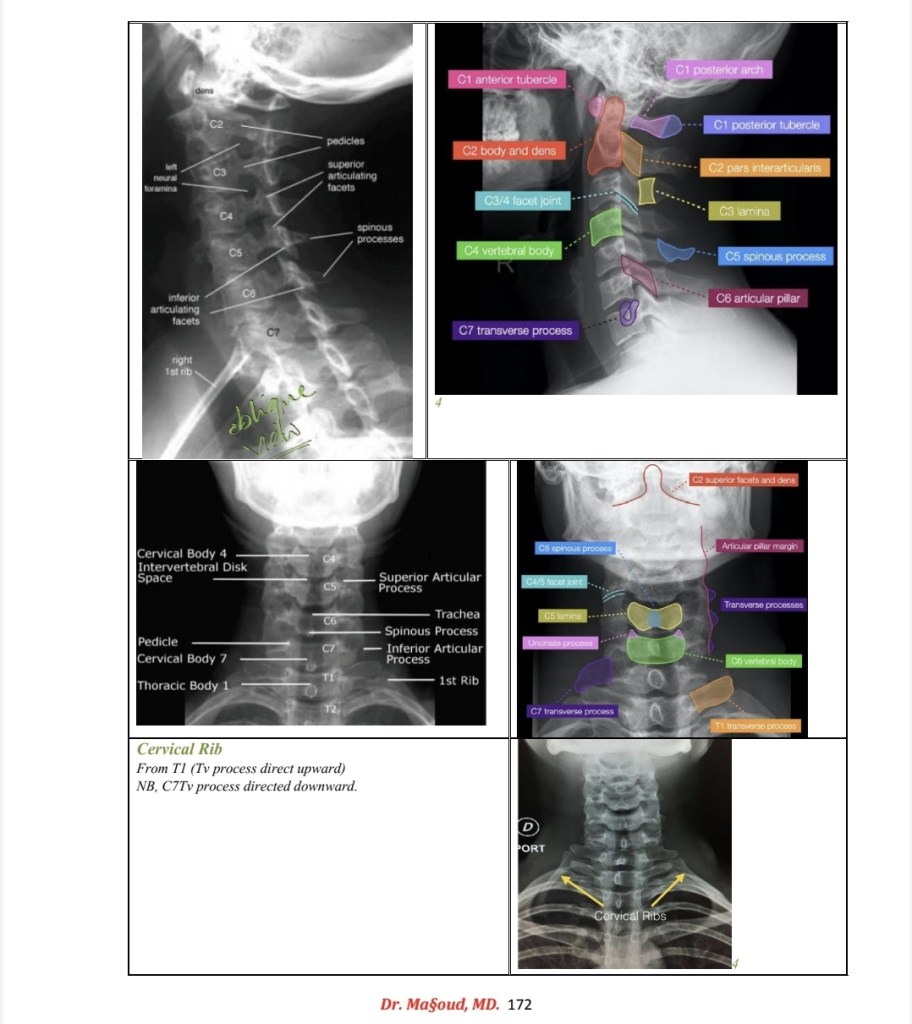

Spine imaging